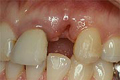

| 通常、歯が一本抜けた場合、両隣の健全な歯を削って、ブリッジしなければなりません。 | ![]() |

| インプラントなら両隣の健全な歯を削りません。 歯の抜けたところへインプラントを埋入し、 自然な歯の形を作ります。 |